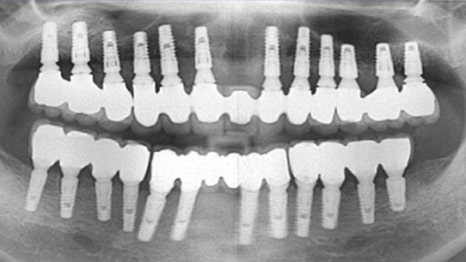

사례

상악(윗니) 틀니를 사용하시던 환자분이

씹는 힘이 약해 대학병원에서 전체 임플란트를

권유받으셨습니다.

비용 부담으로 본원에 내원하셨고,

당뇨 관리와 식생활 개선을 함께 진행한 후

24개를 식립하였습니다.

수술 후에도 내과 협진을 유지하여 혈당을 조절하고

전신 건강이 회복될 수 있도록 도왔습니다.